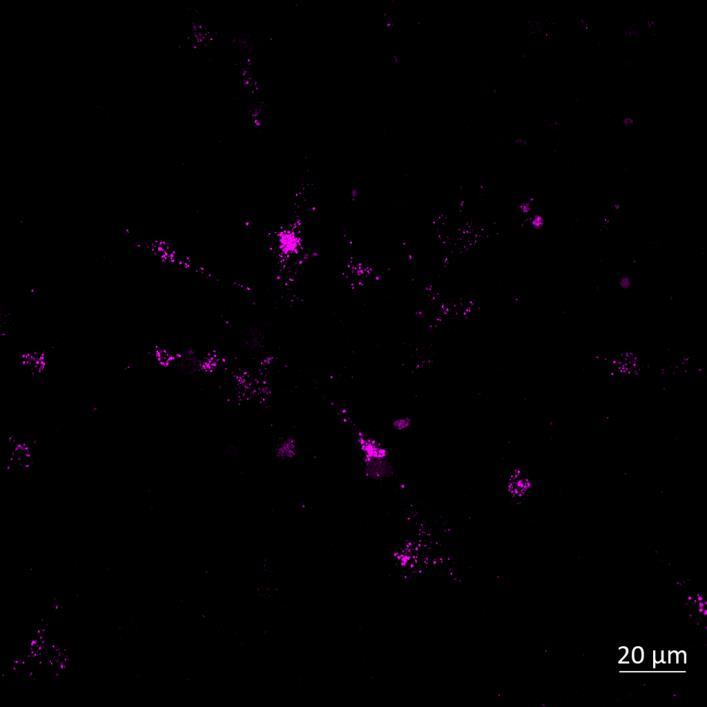

Phosphorylation and Aggregation of Native α-synuclein Induced by Exposure to Seeded Preformed Fibrils

• Microfluidics devices were fixed at 2 or 3 weeks after PFF addition to “donor” chamber

• Immunocytochemistry for β-tubulin and phosphorylated serine 129 α-synuclein was carried out

Lewy body-like perinuclear accumulation of phosphorylated serine 129 α-synuclein (arrows) in response to directly applied and seeded PFFs

• At 2 weeks, phosphorylated αsynuclein was detected in the “donor” chamber neurons only At 3 weeks, phosphorylated αsynuclein was additionally detected in neurons of the “acceptor” chamber

Donor chamber – PFFs directly applied Acceptor chamber – seeded PFFs

D o n o c h a m b r A c e p o c h a m b r D o n o c h a m b r A c e p o c h a m b r 0 2 4 6 8 10 12 0 23 0 0 2weeksafterPFFadditon % p S 1 9 p o s v e -PFF +PFF D o n o c h a m e A c e p o c h a m b e D o n o c h a m e A c e p o c h a m b e 0 2 4 6 8 10 12 08 98 0 0 3weeksafterPFFadditon % p S 1 2 9 p o s v e -PFF PFF Donor chamber – PFFs directly applied Acceptor chamber – seeded PFFs

2 weeks

3 weeks

S129 α-synuclein β-tubulin

α

Phospho-

β-tubulin

-synuclein PFFs

Phospho-S129

-synuclein